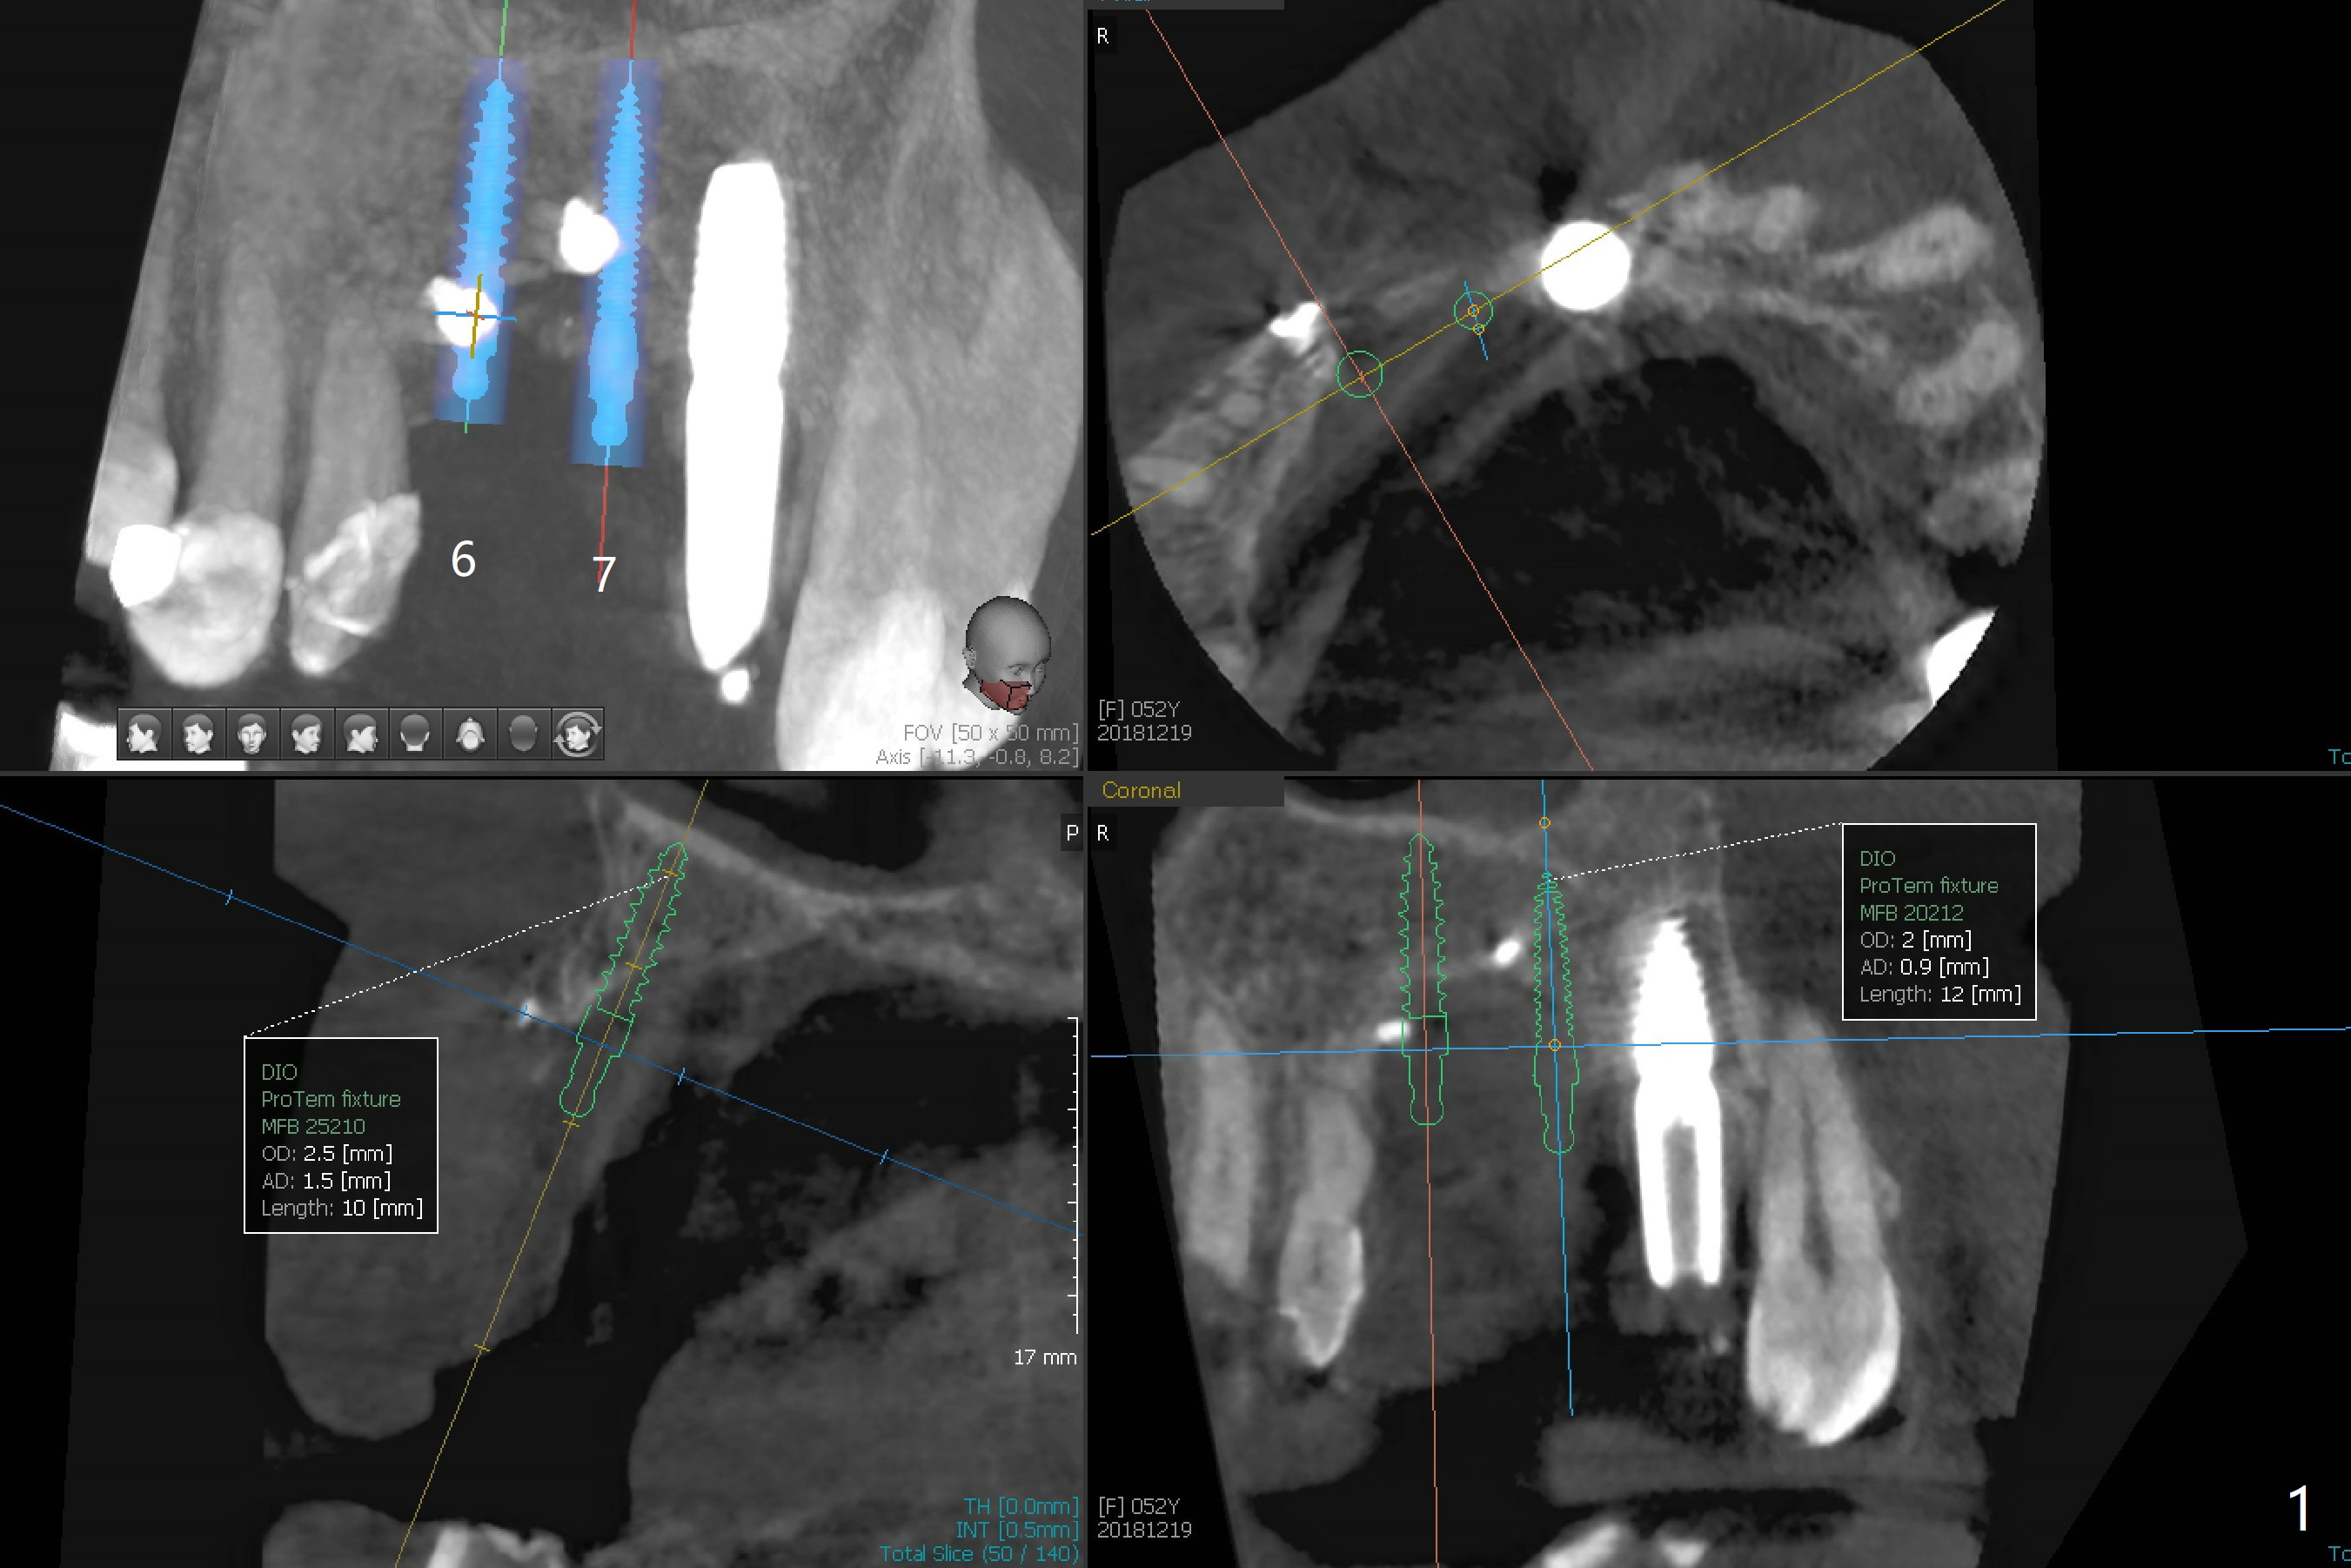

Narrow Implants at #6 and 7

Four months post bone graft with tenting screws at #6 and 7 and implant re-placement at #8, the ridge at #6 and 7 appears to widen slightly, appropriate for narrow implants (Fig.1,2). Guide will be fabricated. The implant at #8 seems to have osteointegrated (Fig.3) with distal gingival recession (Fig.4). One year 5 months later, the tooth #5 is infected with apparently mesial bone loss (Fig.5 *) and papillary erythema and edema (Fig.6). However the pockets are not deep. A gingival embrasure is created between #5 and 6 for self cleansing. The latter does not work. Implants will be placed at #5 and 7 (Fig.7,8).